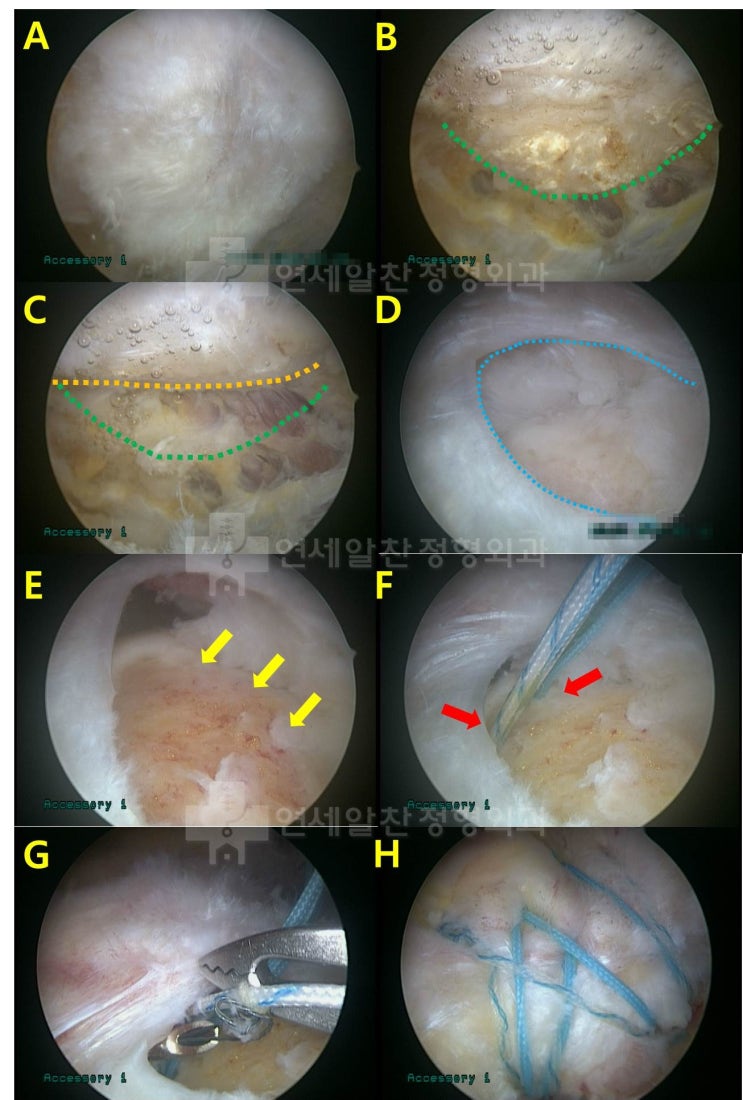

어깨 회전근개 파열 : 보다 단단하게 봉합하는 이열봉합법

안녕하세요. 정형외과 전문의 이동규 입니다. 오늘은 회전근개 파열에서 관절경 수술시 더 단단하게 봉합하...

회전근개파열 에서 이열교량형 봉합법 에 대한 고찰

회전근개 파열 을 수술할 경우 봉합법에 대한 문의를 하는 경우가 종종 있다. 회전근개파열 이 있는 경우 ...

이중교량형 봉합술의 장점

62세 여자환자로 수개월전 부터의 좌측 어깨 통증을 주소로 내원하였다. 농사일을 하시면서 수차례 주사치...